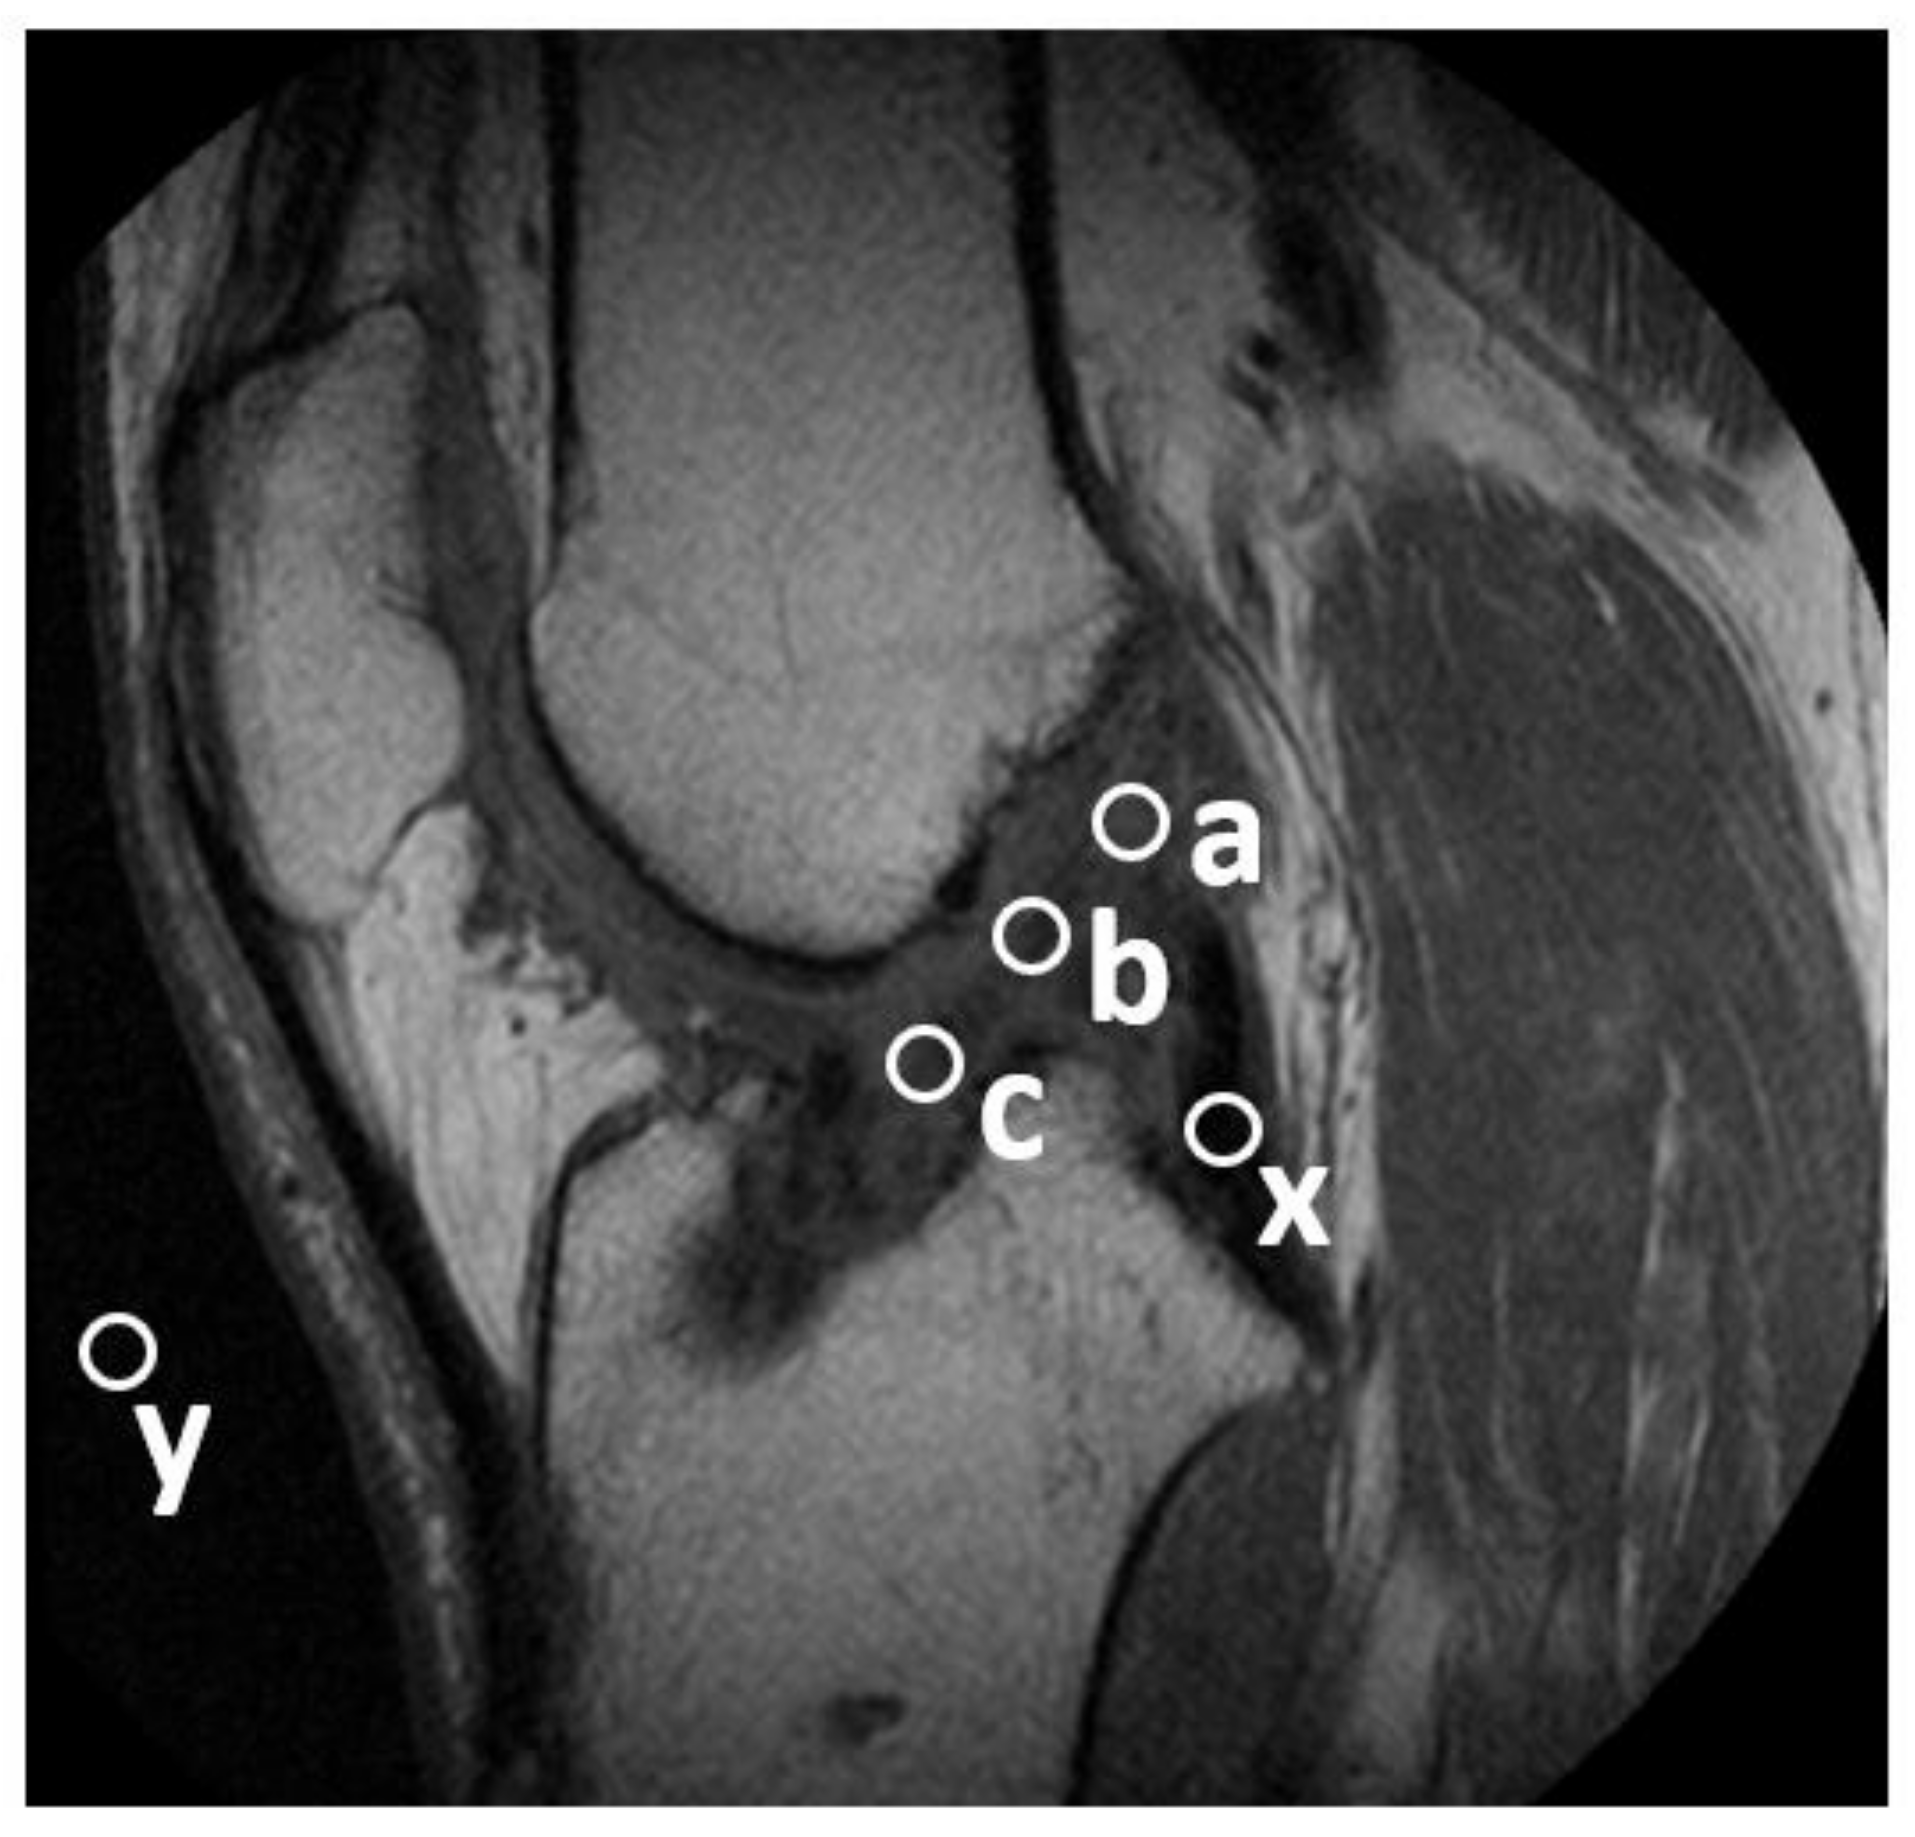

2.7. Tunnel Ganglion Cyst Formation